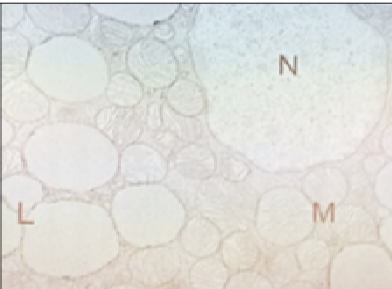

Pour le QCM 7, il ne manquerait pas une photo? Parce ce que s'il s'agit de la photo de gauche, les réponses CD devraient être justes non?